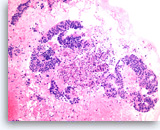

Ductal adenocarcinoma #3,

Pancreas FNA, Cell Block.

The tumor cells form glandular structures with focal loss of cell polarity and stratification. There are also scattered single and small groups of tumor cells. Intracytoplasmic mucin is seen in some of the tumor cells. Note extracellular mucin (right edge) and a background of necrotic cellular debris.

40X